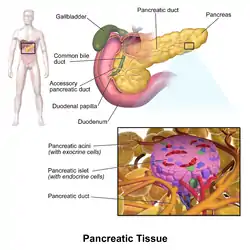

| Pancreatic islets | |

The pancreatic islets or islets of Langerhans are the regions of the pancreas that contain its endocrine (hormone-producing) cells, discovered in 1869 by German pathological anatomist Paul Langerhans.[1] The pancreatic islets constitute 1–2% of the pancreas volume and receive 10–15% of its blood flow.[2][3] The pancreatic islets are arranged in density routes throughout the human pancreas, and are important in the metabolism of glucose.[4]

There are about 1 million islets distributed throughout the pancreas of a healthy adult human, each of which measures an average of about 0.2 mm in diameter.[5]:928 Each islet is separated from the surrounding pancreatic tissue by a thin fibrous connective tissue capsule which is continuous with the fibrous connective tissue that is interwoven throughout the rest of the pancreas.[5]:928

Microanatomy

It has been recognized that the cytoarchitecture of pancreatic islets differs between species.[7][8][9] In particular, while rodent islets are characterized by a predominant proportion of insulin-producing beta cells in the core of the cluster and by scarce alpha, delta and PP cells in the periphery, human islets display alpha and beta cells in close relationship with each other throughout the cluster.[7][9]

The proportion of beta cells in islets varies depending on the species, in humans it is about 40–50%. In addition to endocrine cells, there are stromal cells (fibroblasts), vascular cells (endothelial cells, pericytes), immune cells (granulocytes, lymphocytes, macrophages, dendritic cells) and neural cells.[10]